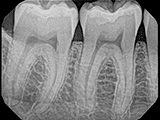

| X-Ray Example |

X-ray taken with the Pro Sensor |

X-ray taken with the Dream Sensor |

X-ray taken with the Open Sensor |

X-ray taken with the Dexis Sensor |

X-ray taken with the Schick 33 Sensor |

rec X-ray taken with the Carestream Sensor |

Dental X-Ray Comparison

DentiMax

X-ray taken with the DentiMax sensor

Open Sensor

X-ray taken with the Caresream® sensor

Dexis

X-ray taken with the Dexis™ sensor

Schick

X-ray taken with the Schick® 33 sensor

Carestream

X-ray taken with the Caresream® sensor

Sensor images and X-rays for the purposes of dental X-ray sensor comparison were produced by DentiMax.